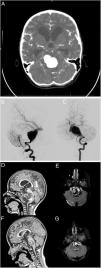

Niña de cuatro años atendida en Urgencias por cefalea intensa y vómitos seguidos de un episodio de pérdida de conocimiento e hipotonía de cinco minutos de duración. La paciente se presentó con palidez cutánea y con una puntuación de 14/15 puntos posibles en la escala de Glasgow. La madre informó que la paciente padecía una jaqueca crónica desde hacía un año. Tras realizarse una tomografía computarizada (TC) (Figura A), se colocó drenaje ventricular externo. La angiografía (Figuras B y C) reveló un aneurisma en la arteria basilar.

A) La TC mostró hemorragia subaracnoidea e hidrocefalia obstructiva.

Angiografía cerebral. Serie de la arteria vertebral izquierda, proyecciones lateral B) y anteroposterior C). Aneurisma gigante fusiforme en los dos tercios inferiores de la arteria basilar. Se descartaron opciones terapéuticas como el sacrificio del vaso principal o la reconstrucción asistida con stent por la edad de la paciente y consideraciones anatómicas.

Secuencias T1 y recuperación de la inversión atenuada de fluido (FLAIR) de RM: postoperatorio inmediato (D y E) y seis meses de postoperatorio (F y G). Las imágenes muestran una reducción progresiva del saco aneurismático y resolución parcial del efecto masa y la hidrocefalia obstructiva.

Se descartaron el sacrificio del vaso parental o la reconstrucción asistida con stent como opciones terapéuticas debido a la edad de la paciente y consideraciones anatómicas. La reversión del flujo de la arteria principal se consideró como el abordaje óptimo, ya que el test de oclusión con balón de la arteria vertebral izquierda única (con hipoplasia extrema de la arteria vertebral derecha), realizado bajo monitorización neurofisiológica, produjo una desviación adecuada del flujo basilar. Por lo tanto, el aneurisma se manejó mediante la oclusión endovascular de la arteria vertebral izquierda pasada la arteria cerebelosa posterior. Se realizó resonancia magnética (RM) tras la intervención endovascular (Figuras D-G). La paciente recibió el alta a los 34 días, sin secuelas neurológicas.